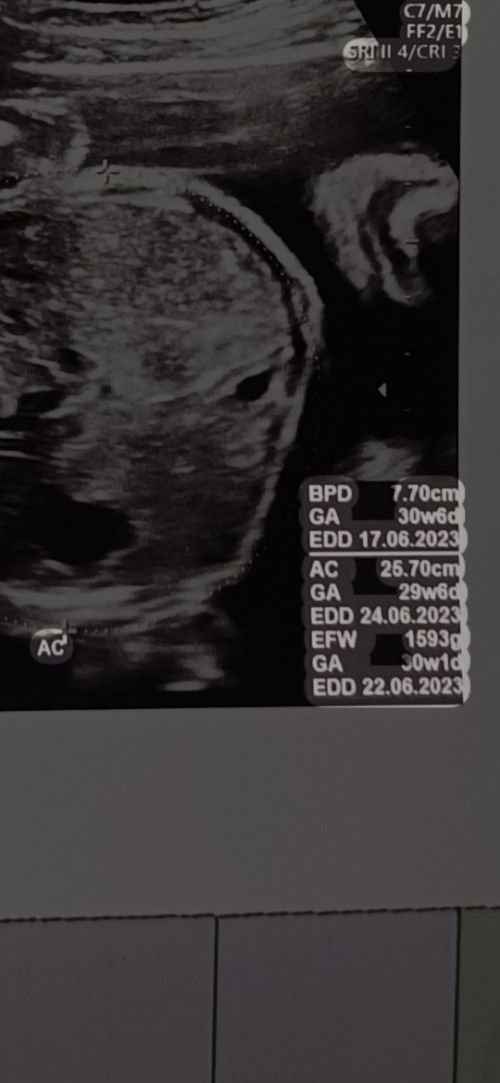

Hitung HPL nya sebaiknya dari HPHT saja. Keterangan gambar yg ibu beri itu adalah HPL berdasarkan BPD (diameter parietal kepala), AC (lingkar perut), HC (lingkar kepala) dan EFW alias bbj alias berat badan janin

itu hpl nya bunda ambil yg paling jauh Bun 22 bulan ke 6, syukur2 lahirannya maju banyak cukup bulan. klo ambil tgl yg tercepat khawatir blm lahir jadi lewat hpl. hpl berubah2 artinya masih aman klo ditunggu smp tgl segitu

pasti beda karna disitu ada 3 perhitungan. ada menurut lingkar kepala, lingkar perut dan berat janin. makananya biasanya usg TM2&3 HPL tidak akan akurat karna dihitung dr pertumbuhan janin. paling akurat adalah USG TM1 kalau binggung ikut hpht saja semoga haidnya lancar biar bisa kepake

untuk hpl yg akurat itu ngikutin terakhir mens ya bun kata bidan aku, kalo USG itu hpl nya diukur dari ukuran bayi nya bisa maju kalo bayi nya besar bisa mundur hpl nya kalo bayi nya kecil

klo bunda sering usg hpl pasti beda" bun biasanya semakin maju, tapi yg akurat awal usg bun biasanya dibawah usia kandungan 20w masih akurat